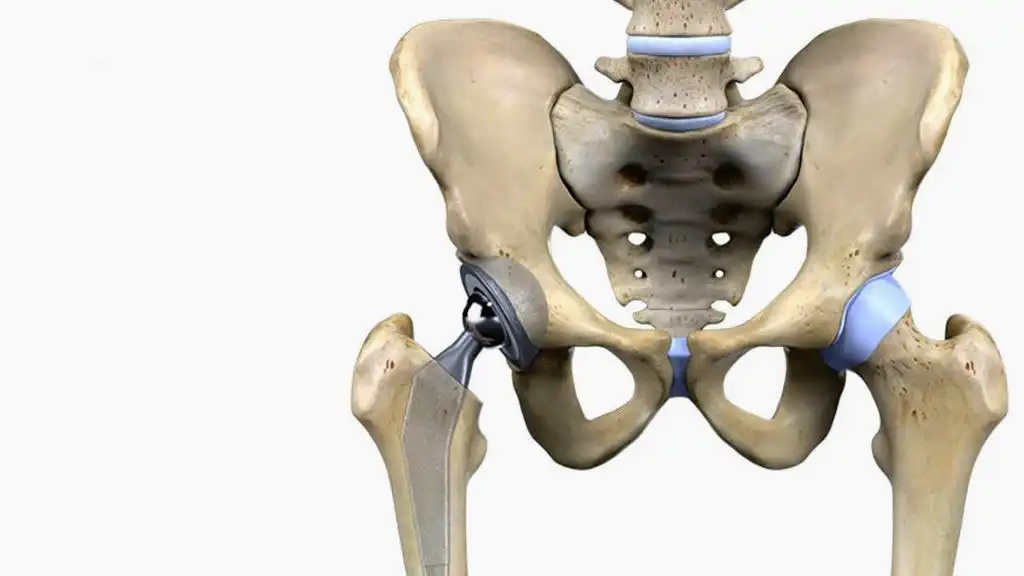

جراحی مفصل شانه در سال 1405 | قیمت، نکات طلایی و راهنمای قدمبهقدم برای بازگشت بدون درد ادامه مطلب »